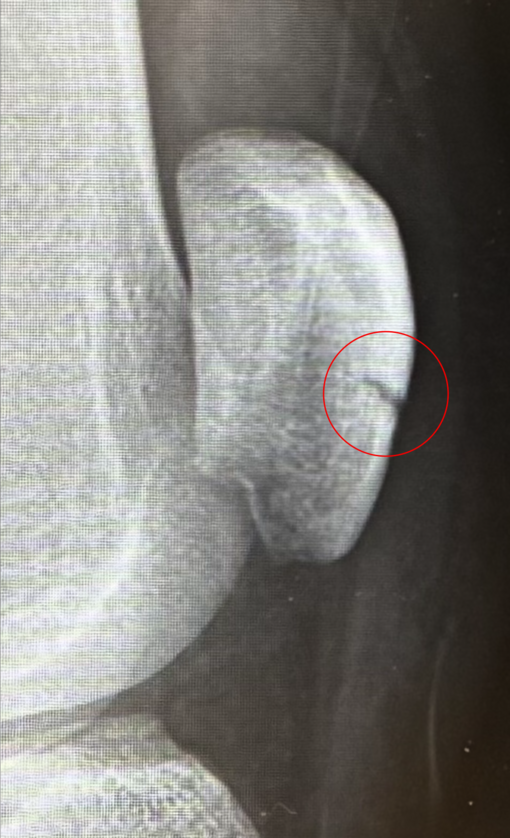

03/02 17:48 UP! 膝の骨折から2週間、、、TAKUMI(タクミ)(30歳)

TAKUMI(タクミ) 膝の骨折から2週間、、、

膝の骨折から2週間。

経過観察でレントゲンを撮りにいって、経過は順調。

ようやく少しずつ痛みが引いてきて、今日から「曲げる練習」もスタート。

まだ先は長そうだけど、一歩ずつ進むしかないので焦らず頑張ります!!